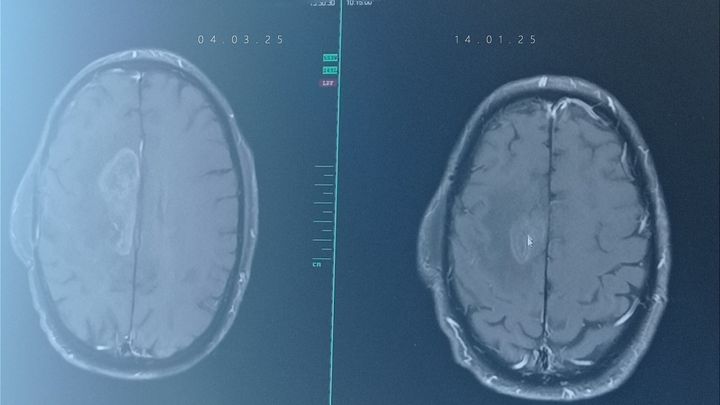

Nach der ersten Operation folgten Bestrahlung und Chemotherapie, doch der Tumor wuchs erneut. Eine zweite Operation leider dadurch halb gelähmt, mittlerweile wieder aber so gut wie es geht wieder am laufen.. weitere Chemotherapien sowie die Behandlung mit Stivarga schienen Hoffnung zu geben, doch leider zeigen die letzten Untersuchungen wieder Zellwachstum.

Die Nebenwirkungen von Stivarga sind jedoch extrem belastend und machen ihn mehr zu schaffen als die vorherige Behandlung. Am 14.02 der erneute MRT Termin sieht wohl auch nicht so gut aus, das wieder Krebszellen zusehen sind. was weiter hin auf uns zu kommen wird können wir nicht sagen. Trotz allem kämpfen wir weiter – Tag für Tag. Wir sind dankbar für jede Unterstützung und jede gute Erinnerung, die uns hilft, die schwere Zeit zu überstehen.